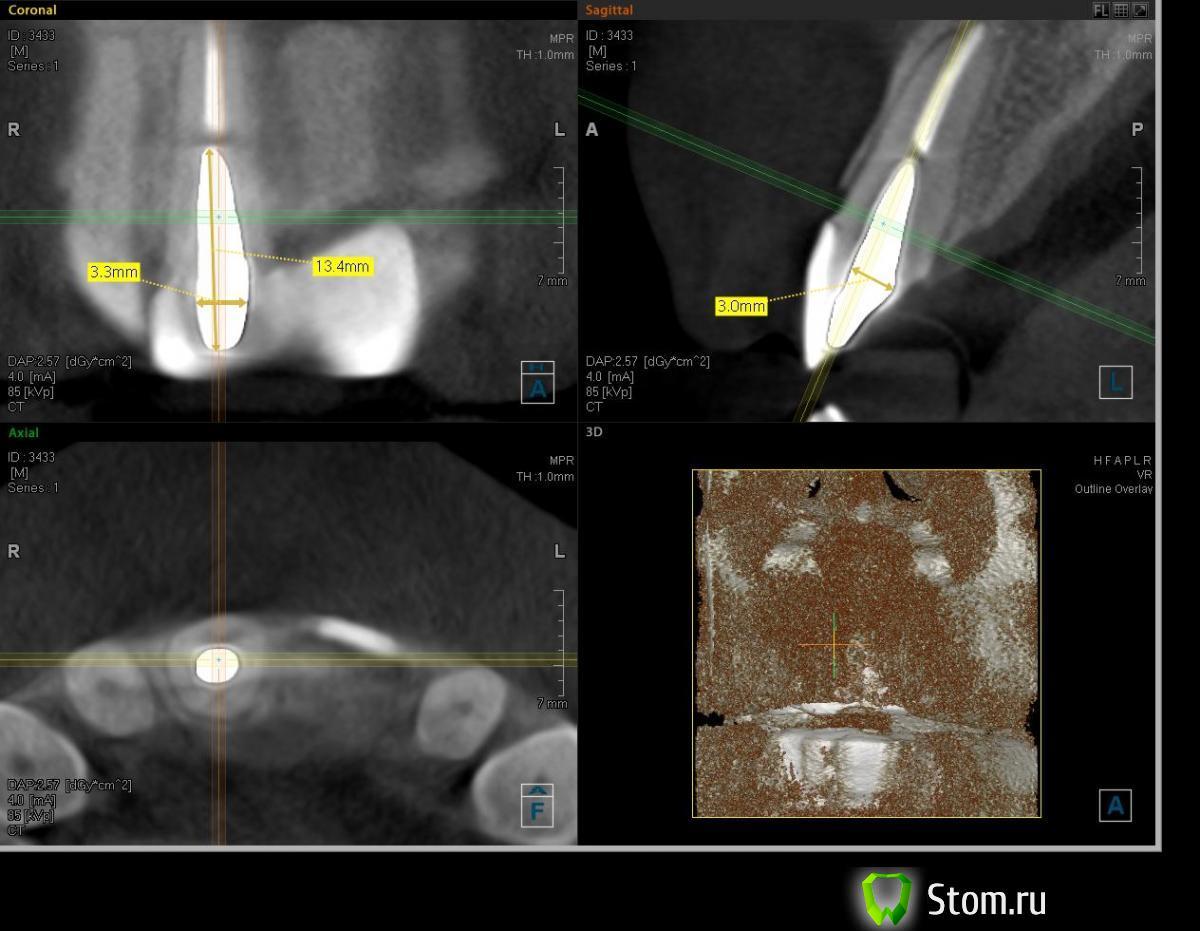

leon_id Опубликовано 22 ноября, 2011 Автор Поделиться Опубликовано 22 ноября, 2011 Спасибо за ответы. Вот я и пытаюсь найти врача :-) Пока не очень успешно, к сожалению.Был на 2-х консультациях, один врач говорит о том, что надо ставить только МК коронки с плечевой массой, потому как диоксид циркония хрупок и может колоться, и не готов давать гарантий на коронки из доксида.Второй говорит о том, что коронка из диоксида циркония стоять на МК вкладке долго не сможет (разный к-т теплового расширения :-)) А делать одну коронку из диоксида, а вторую - из МК как-то странно.Про е.max никто из докторов даже не говорил... И по вкладке есть еще вопрос (фото прикрепил) - я ее нижним зубом касаюсь (совсем чуть-чуть, но все-таки...). И первый доктор сказал, что не факт, что удасться сделать нормально коронку - придется вкладку точить и она сломаться может.Хотелось бы получить от вас независимое мнение по этому вопросу - какова минимальная толщина вкладки?. Честно не помню, из чего вкладка - или титан, или КХС. Может вкладку переделать? PS уже начинаю подумывать о том, что надо в Питер ехать лечиться :-) Ссылка на комментарий

Doc Опубликовано 23 ноября, 2011 Поделиться Опубликовано 23 ноября, 2011 Про хрупкость ДЦ Ваш доктор немного погорячился. Судя по всему просто не работает с этими технологиями. ДЦ прочнее, чем многие металлы. Про разный к-т тоже как-то все сомнительно. Стоят вроде годами и ничего. Толщина вкладки в Вашем случае большой роли не сыграет, там полно запаса, а сзади ДЦ можно в этом месте хоть вообще не облицовывать. Но сказать что-то конкретное по одному снимку сложно, нужно видеть прикус и ситуацию во рту. В общем, ищите доктора дальше. Здесь в форуме полно врачей из Москвы. Ссылка на комментарий